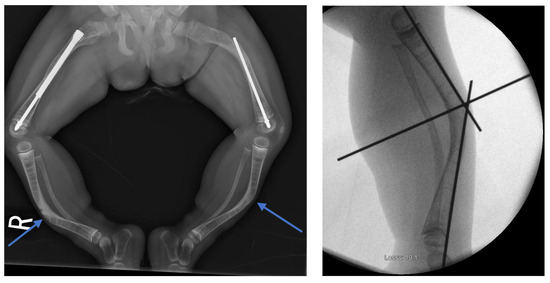

Figure 8.

Preoperative and intraoperative X-rays of the lower extremities showing tibia deformities/fractures. Blue arrows indicate the CORAs.

Figure 9.

(A–H): Series of intraoperative fluoroscopy images demonstrating insertion of the SLIM nail. (A) After osteotomy, the fracture is reduced. (B) Lateral view of proximal reaming through the osteotomy site. (C) AP view of proximal reaming through the osteotomy site. (D) Lateral view of distal reaming through the osteotomy site. (E) AP view distal reaming through the osteotomy site. (F) Insertion of the SLIM nail. (G) SLIM nail is gradually advanced past the osteotomy site. (H) AP view of installed SLIM nail, with proximal threading in the epiphysis.